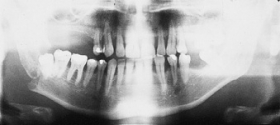

The primary purpose of the consultation is the outpatient follow-up treatment and care of patients who have undergone surgery following bone injuries to the upper and/or lower jaw. In addition to patients with fractures of the facial skull, patients with injuries to the teeth and facial soft tissues are also followed up.